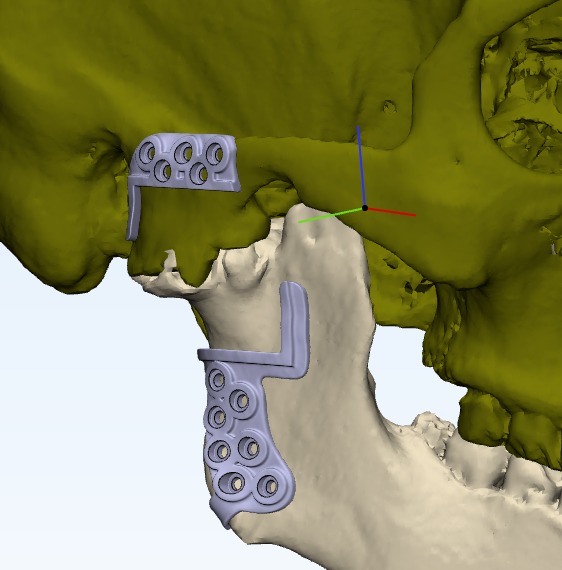

Tmj anklosys leading to deficient mandible and deficient chin corrected by TMJ Surgery followed by Orthognathic surgery